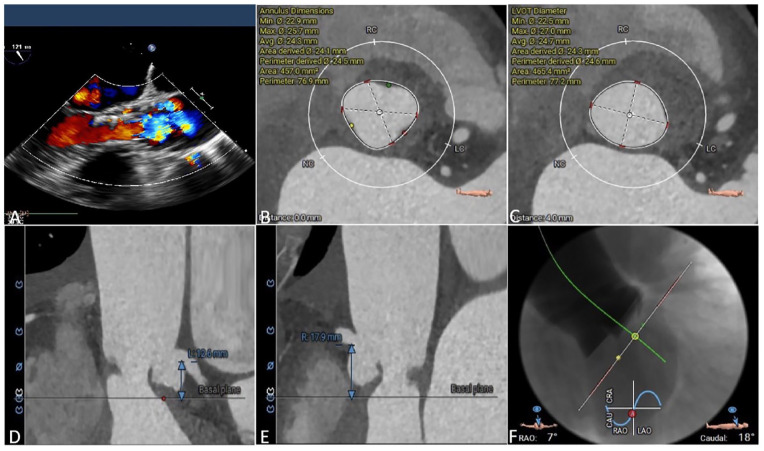

Methods: A total of 9 patients with severe AS accepted TAVR using Xcor system with transapical access in our center. Clinical outcomes were collected at baseline, before discharge, and at the 30-day follow-up.

Results: All patients achieved procedural success, postprocedural transesophageal echocardiography showed that all of the patients had no/trace paravalvular leakage. The mean AV pressure gradient decreased from 50 mmHg (range 18-76 mmHg) to 10 mmHg (range 8-14 mmHg) (P < .001). At the 30-day follow-up, all patients had an improvement of ⩾1 New York Heart Association functional class (P < .001). The average 6-minute walk distance (377.2 [range 330.0-430.0] m vs 276.1 [range 245.0-320.0] m, P < .001) and Kansas City cardiomyopathy questionnaire score (53.4 [range 45.0-62.0] vs 38.9 [range 35.0-43.0], P < .001) were both improved.

Conclusions: Our early experience shows that the Xcor system is safe and feasible in the treatment of patients with severe AS.